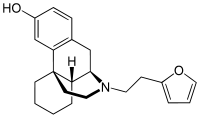

Morphinan derivatives

- Butorphanol—agonist/antagonist